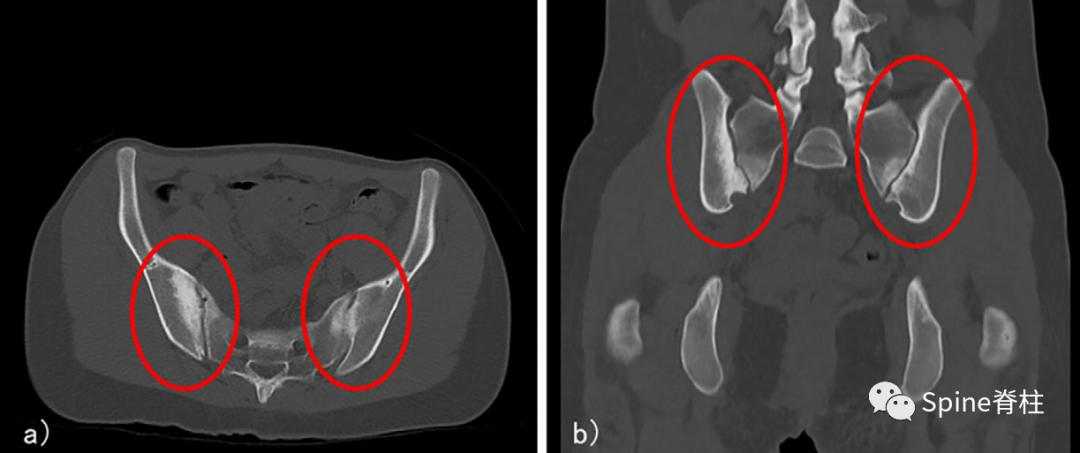

CT提示主要发生在靠近两个骶髂关节的髂骨侧骨硬化,未观察到关节不规则、侵蚀或关节间隙变窄